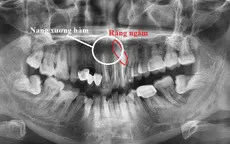

VTV.vn - Trung tâm Răng Hàm Mặt, Bệnh viện đa khoa Hùng Vương (Phú Thọ) vừa tiếp nhận bệnh nhân nam 51 tuổi (trú tại Hạ Hoà, Phú Thọ) đến khám vì sưng đau môi trên.